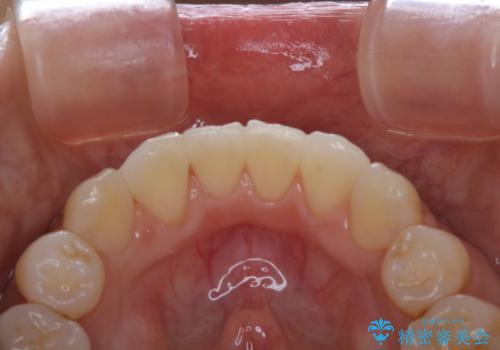

- 約1年前に矯正治療が終了し、その後のメンテナンスを行っている方です。矯正のチェックもかねてクリーニングも希望とのことでした。

PMTC(自費クリーニング)30分コースを行いました。

定期的なメンテナンスをして頂いていること、ご自身でのケアをかなり丁寧にされていていることで、歯石や着色の量がさほど多くなかったため30コースで全体的なクリーニングが可能でした。

矯正治療が終了した後は、歯並びの改善により歯ブラシやフロスが通しやすくなります。ただし、日々の磨き残しや唾液の成分などによりバイオフィルムや歯石はどうしても付着してしまいます。そのため、2~3か月に1回は、歯科医院での専門的クリーニングをすることが大切です。